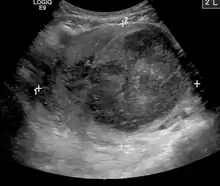

Also common to all intervention radiology procedures are the medical imaging machines that allow the healthcare provider to see what is occurring within the body. Some use X-rays (such as CT and fluoroscopy) and some do not (such as ultrasound and MRI).[1] In each case, the images created may be modified by computer to better visualize the structures as is in the case with digital subtraction angiography, CT and MRI, or the display of the images improved with virtual reality or augmented reality presentation.[2]

The workup for the procedure is straightforward and the interventional radiologist performing the procedure often orders several tests to assess how well the patient will tolerate the procedure. These are often simple blood tests, and an ultrasound of the heart and liver. The procedure is often well tolerated and can result in a permanent reduction or elimination of symptoms. The procedure can take anywhere between 15 minutes to an hour and has lower risks of bleeding or infection compared to an equivalent surgical procedure.[19]